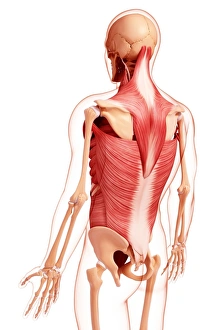

The scapula, also known as the shoulder blade, is a crucial bone in our body that plays a significant role in our mobility and stability. It forms part of the pectoral girdle and connects the upper arm to the thorax. When we examine diagrams of the bones of the hand and arm, we can see how intricately connected they are to the scapula. This connection allows us to perform various movements with precision and control. In an anterior view total shoulder joint repair image, we witness medical advancements aimed at restoring functionality to this vital joint. The intricate procedure highlights just how important it is to maintain a healthy scapula for optimal movement. Shoulder muscles artwork showcases their attachment points on the scapula, emphasizing their role in providing strength and stability during physical activities. Understanding these muscles helps us appreciate their contribution to everyday tasks like lifting or throwing. A front view of female anatomy highlighting the endocrine system reminds us that even though not directly related to the scapula, every part of our body works together harmoniously. Hormones secreted by glands within this system influence bone health and development. An anterior view of human skeletal system with labels gives us a comprehensive understanding of where exactly our scapula fits into this complex framework. It serves as an anchor point for numerous ligaments and tendons essential for proper functioning. Pictograms on an ox scapula depict ancient rituals performed to ward off danger—a testament to how cultures throughout history recognized its significance beyond mere anatomy. These artifacts remind us that humans have long understood its importance in daily life. The skeleton of an eagle after Milne-Edwards engraving demonstrates nature's adaptation at its finest—the bird's wingspan relies heavily on strong shoulder blades (scapulas) allowing it effortless flight through vast skies. Haydon's Curtius engraving captures another artistic representation showcasing human form—this time focusing on muscular structure including the scapula.